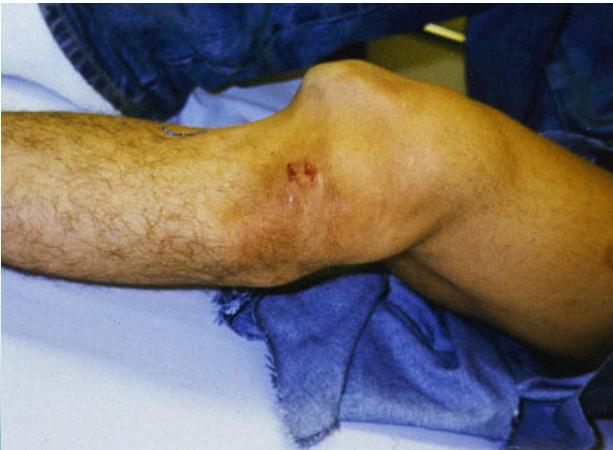

Knee (Tibiofemoral) Dislocation

- High energy: usually RTA

- Gross deformity – must examine neurovascular status

- Popliteal artery at risk